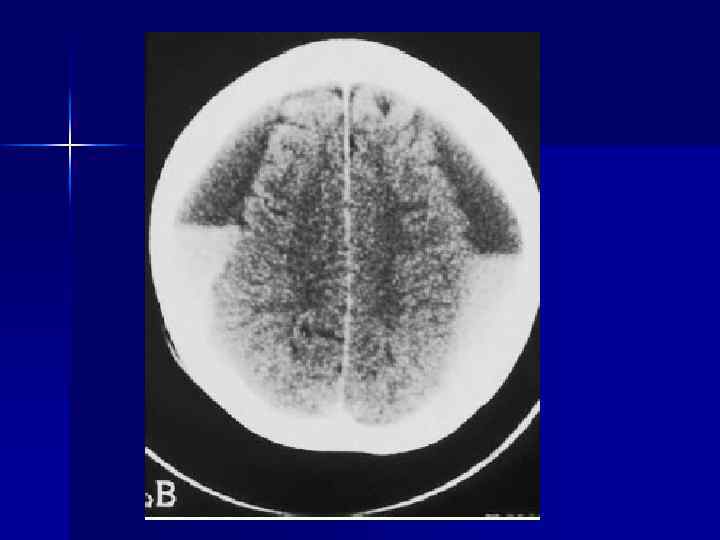

I. Внутримозговые повреждения • первичные -Диффузное аксональное повреждение (ДАП) - Очаговые ушибы ( + разрывы эпендимы желудочков, воронки гипофиза + повреждения черепно-мозговых нервов (III, IV, VI и др. ) - Внутримозговые гематомы

Первичные повреждения Диффузное аксональное повреждение (ДАП) Механизм – ускорение / торможение, ротация Локализация – полушария головного мозга - граница серого и белого вещества - лобные и теменные доли (50%) - базальные ганглии - мозолистое тело (валик) - средний мозг (дорсальные отделы) Диагностика: - КТ информативна только в 10% случаев. - МРТ ≈ 93%

КТ : ДАП в сочетании с очагами ушибов